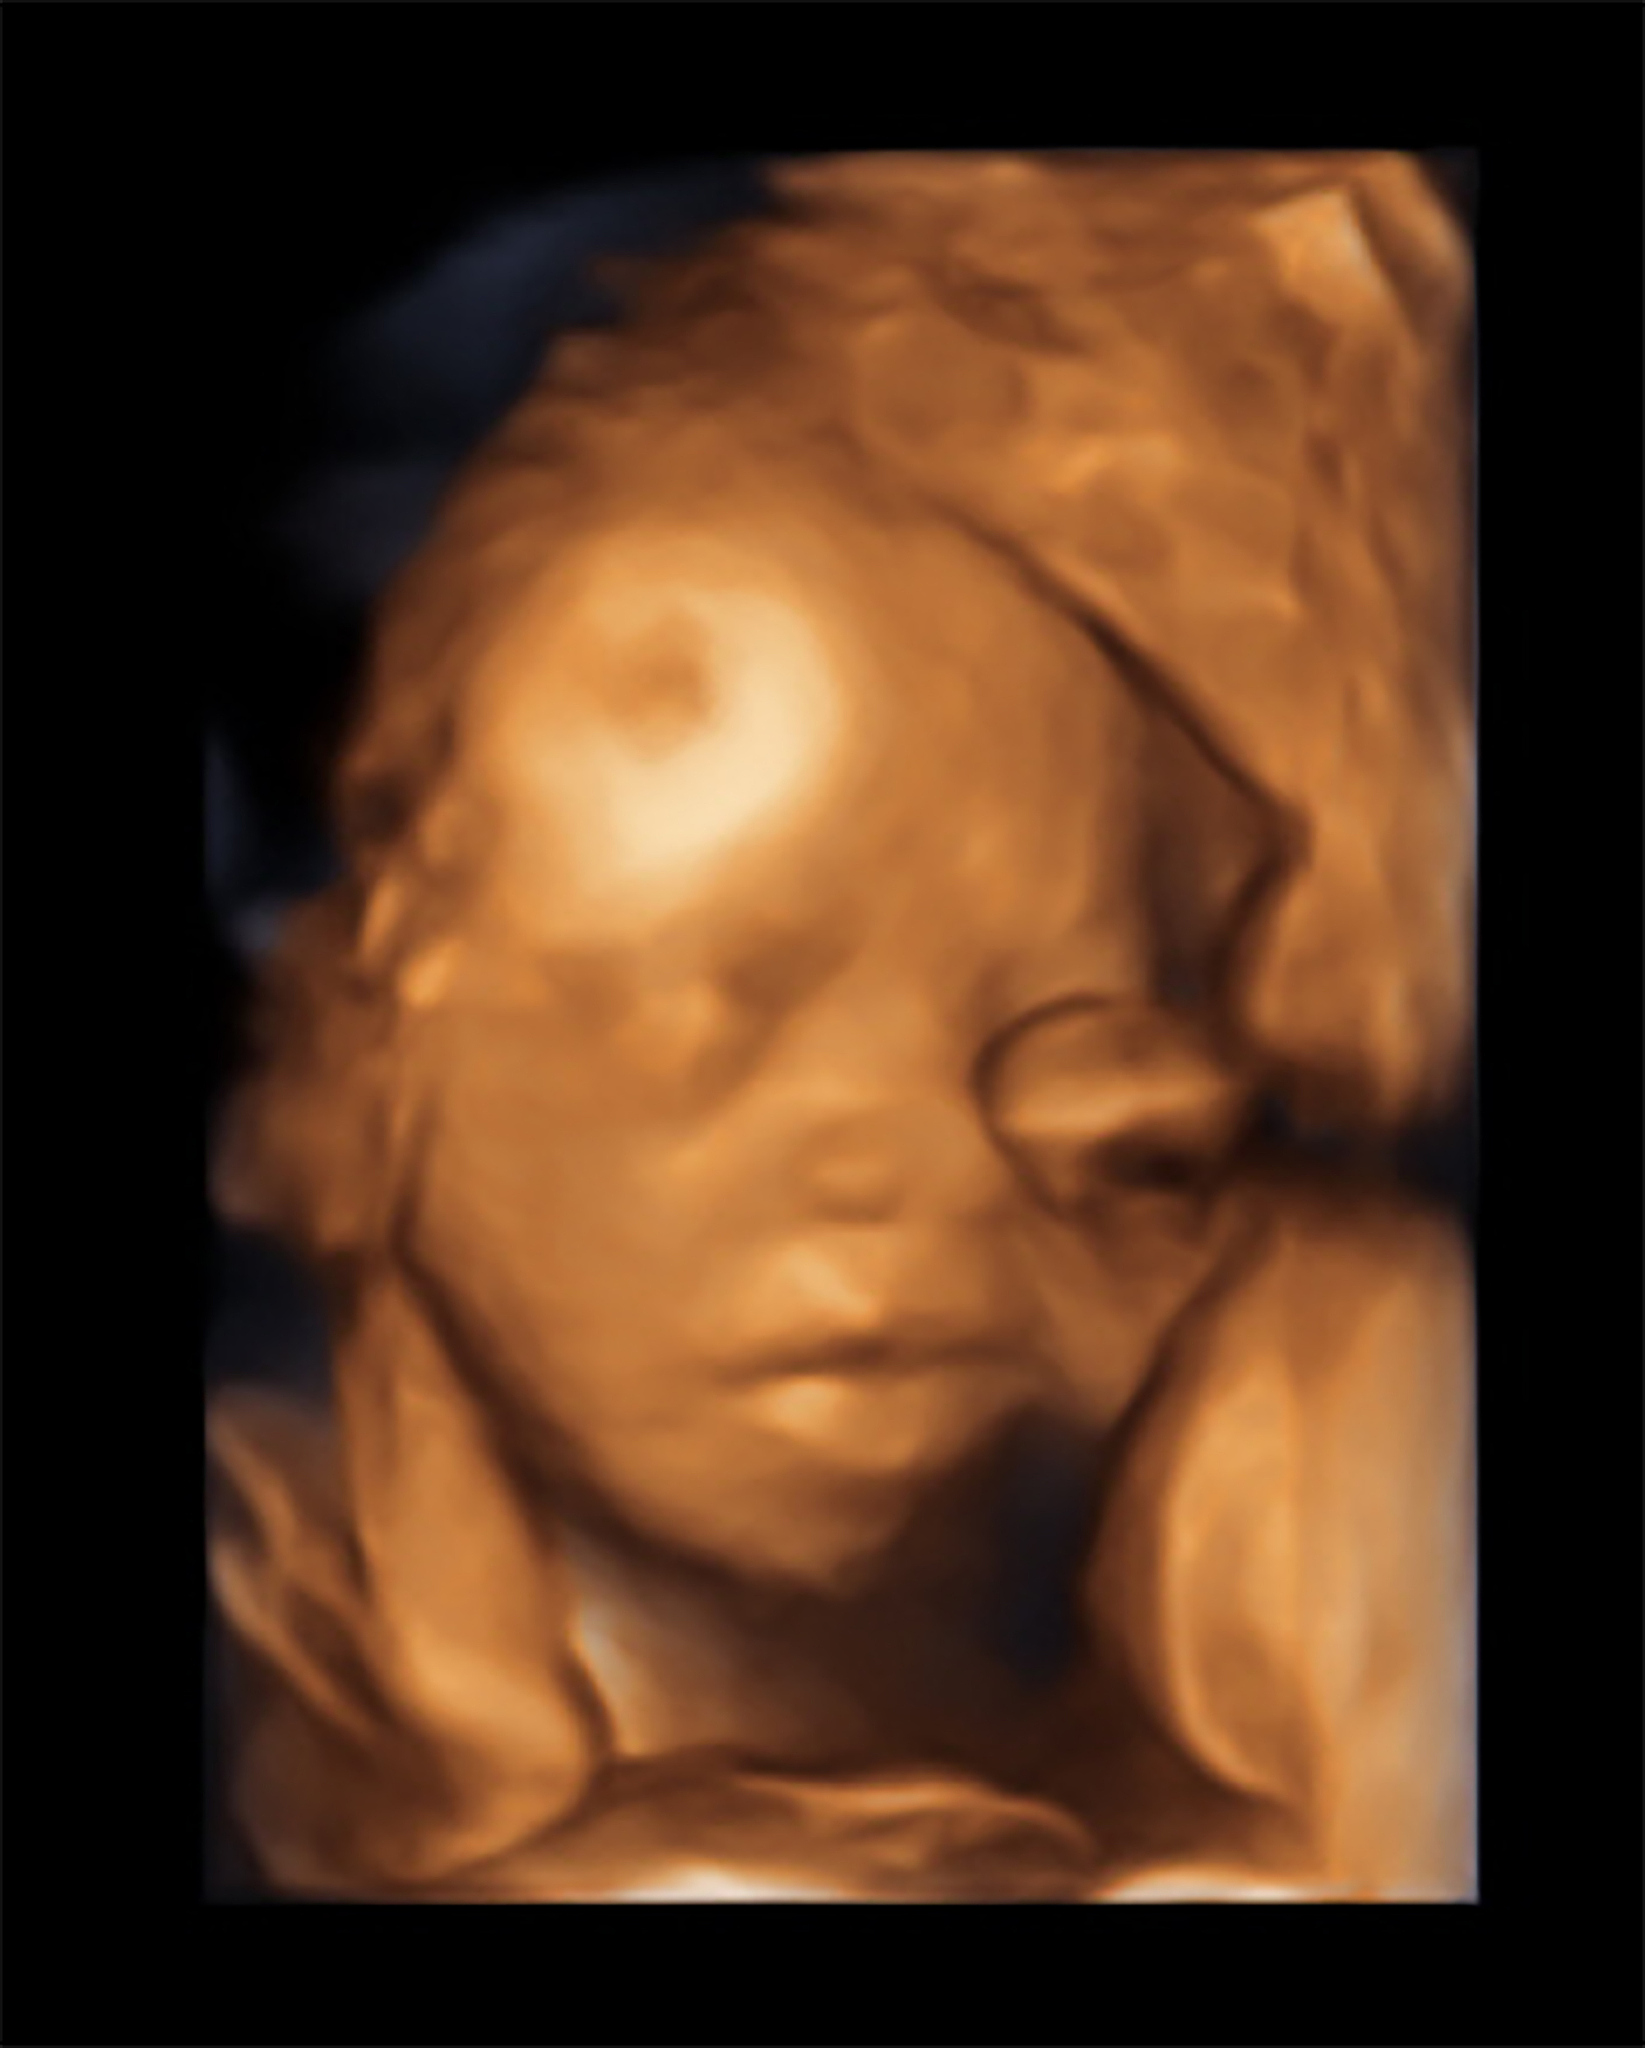

胎儿四维超声不能排查所有畸形,只能发现大部分结构性畸形。四维超声能清晰显示胎儿的面部、四肢、内脏等结构,可排查唇腭裂、脑积水、肢体畸形、心脏缺损等常见畸形。